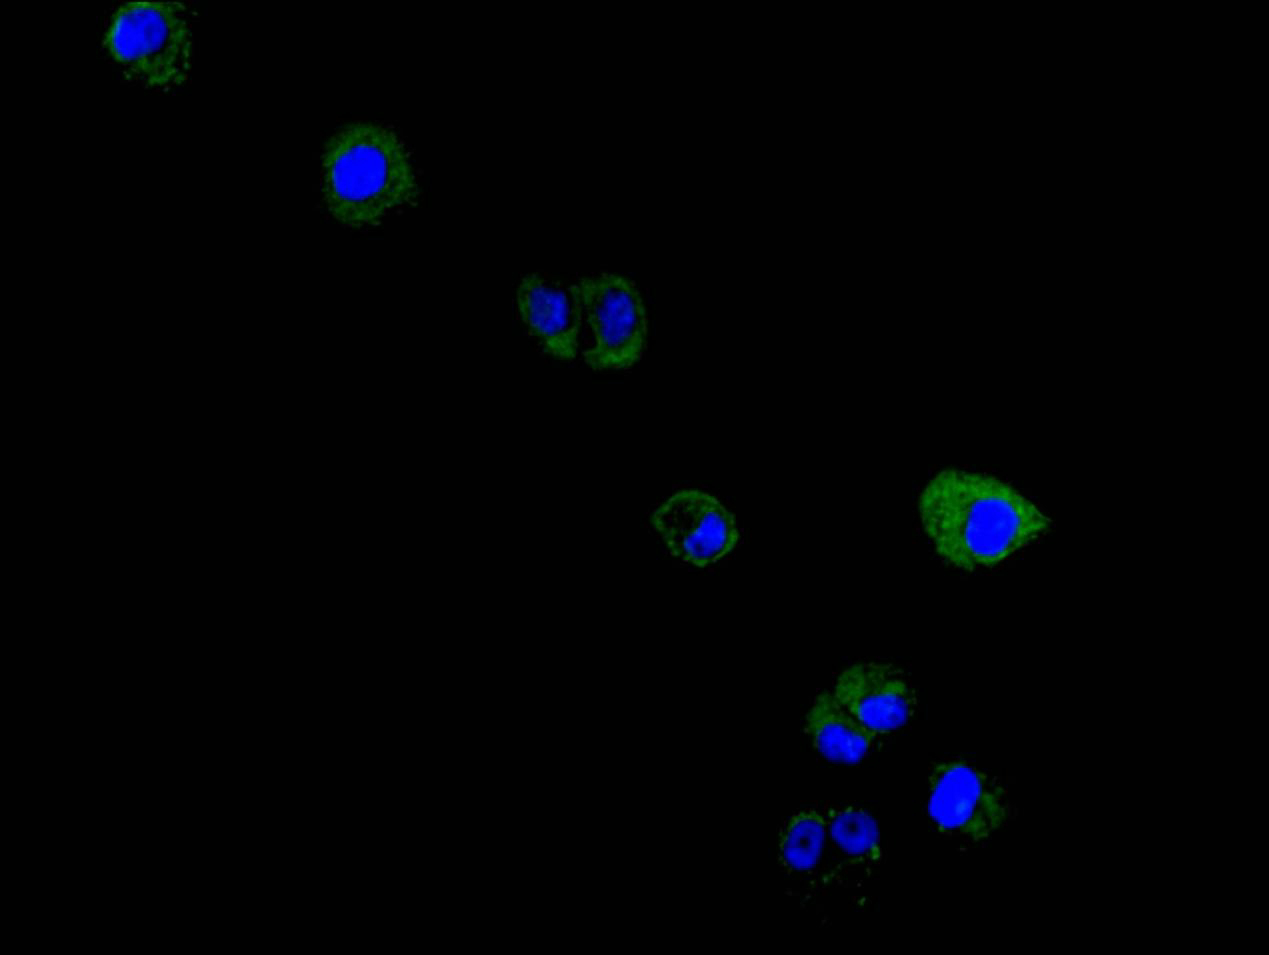

Immunofluorescence staining of Hela cell with CSB-RA015007MA4HU at 1:150, counter-stained with DAPI. The cells were fixed in 4% formaldehyde and blocked in 10% normal Goat Serum. The cells were then incubated with the antibody overnight at 4C. The secondary antibody was FITC-conjugated AffiniPure Goat Anti-Mouse IgG(H+L)

Immunofluorescence staining of MCF7 cell with CSB-RA015007MA4HU at 1:150, counter-stained with DAPI. The cells were fixed in 4% formaldehyde and blocked in 10% normal Goat Serum. The cells were then incubated with the antibody overnight at 4C. The secondary antibody was FITC-conjugated AffiniPure Goat Anti-Mouse IgG (H+L)